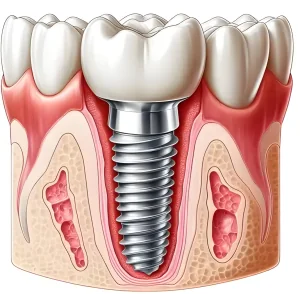

Implant dentistry